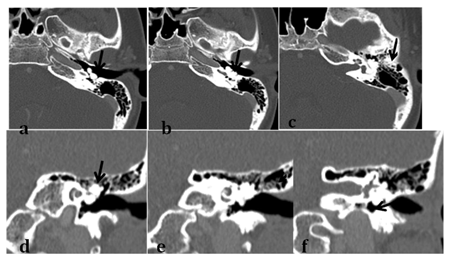

Figure 3 Axial image displaying middle ear Osteoma (black arrow) is well separated from carotid canal (c) and intimately related to but still separated from cochlear promontory (grey arrows).

Abbreviations: CO, basal turn of cochlea.